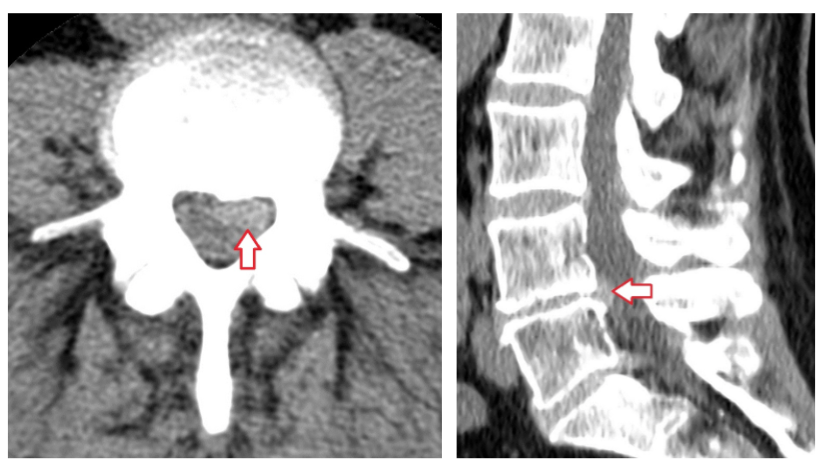

КТ-протрузии дисков: Визуализация и классификация

Раздел: Необычные решения